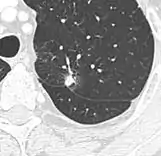

subpleural nodule.[9]

Round well-delineated solid lung nodule with smooth border.[9]